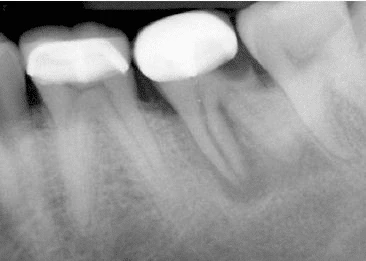

- Hình 14. Tiêu xương rộng khu trú quanh một răng, những răng cạnh đó bình thường, gợi ý một trường hợp nứt dọc chân răng

Hình 15. Khi răng có ống tuỷ rộng hơn so với răng cùng loại hoặc so với răng cạnh nó thì nên nghi ngờ có nứt dọc chân răng